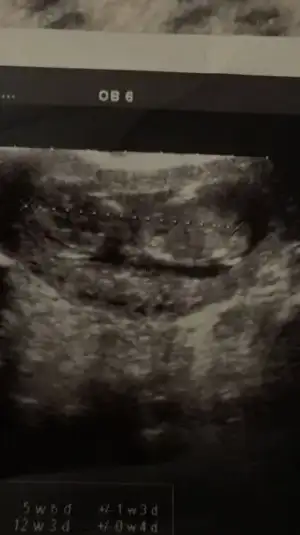

Canım benim usg lerin hiç birinde çıkıntı yok en son yandan usg var ondada hiç bişi yok canım bak ilk foto 10+2 ikinci 12+5

• 2AD2EE83-ABE2-4876-B0EF-E037CB8DCFBC.webp

2AD2EE83-ABE2-4876-B0EF-E037CB8DCFBC.webp

8,3 KB · Görüntüleme: 51